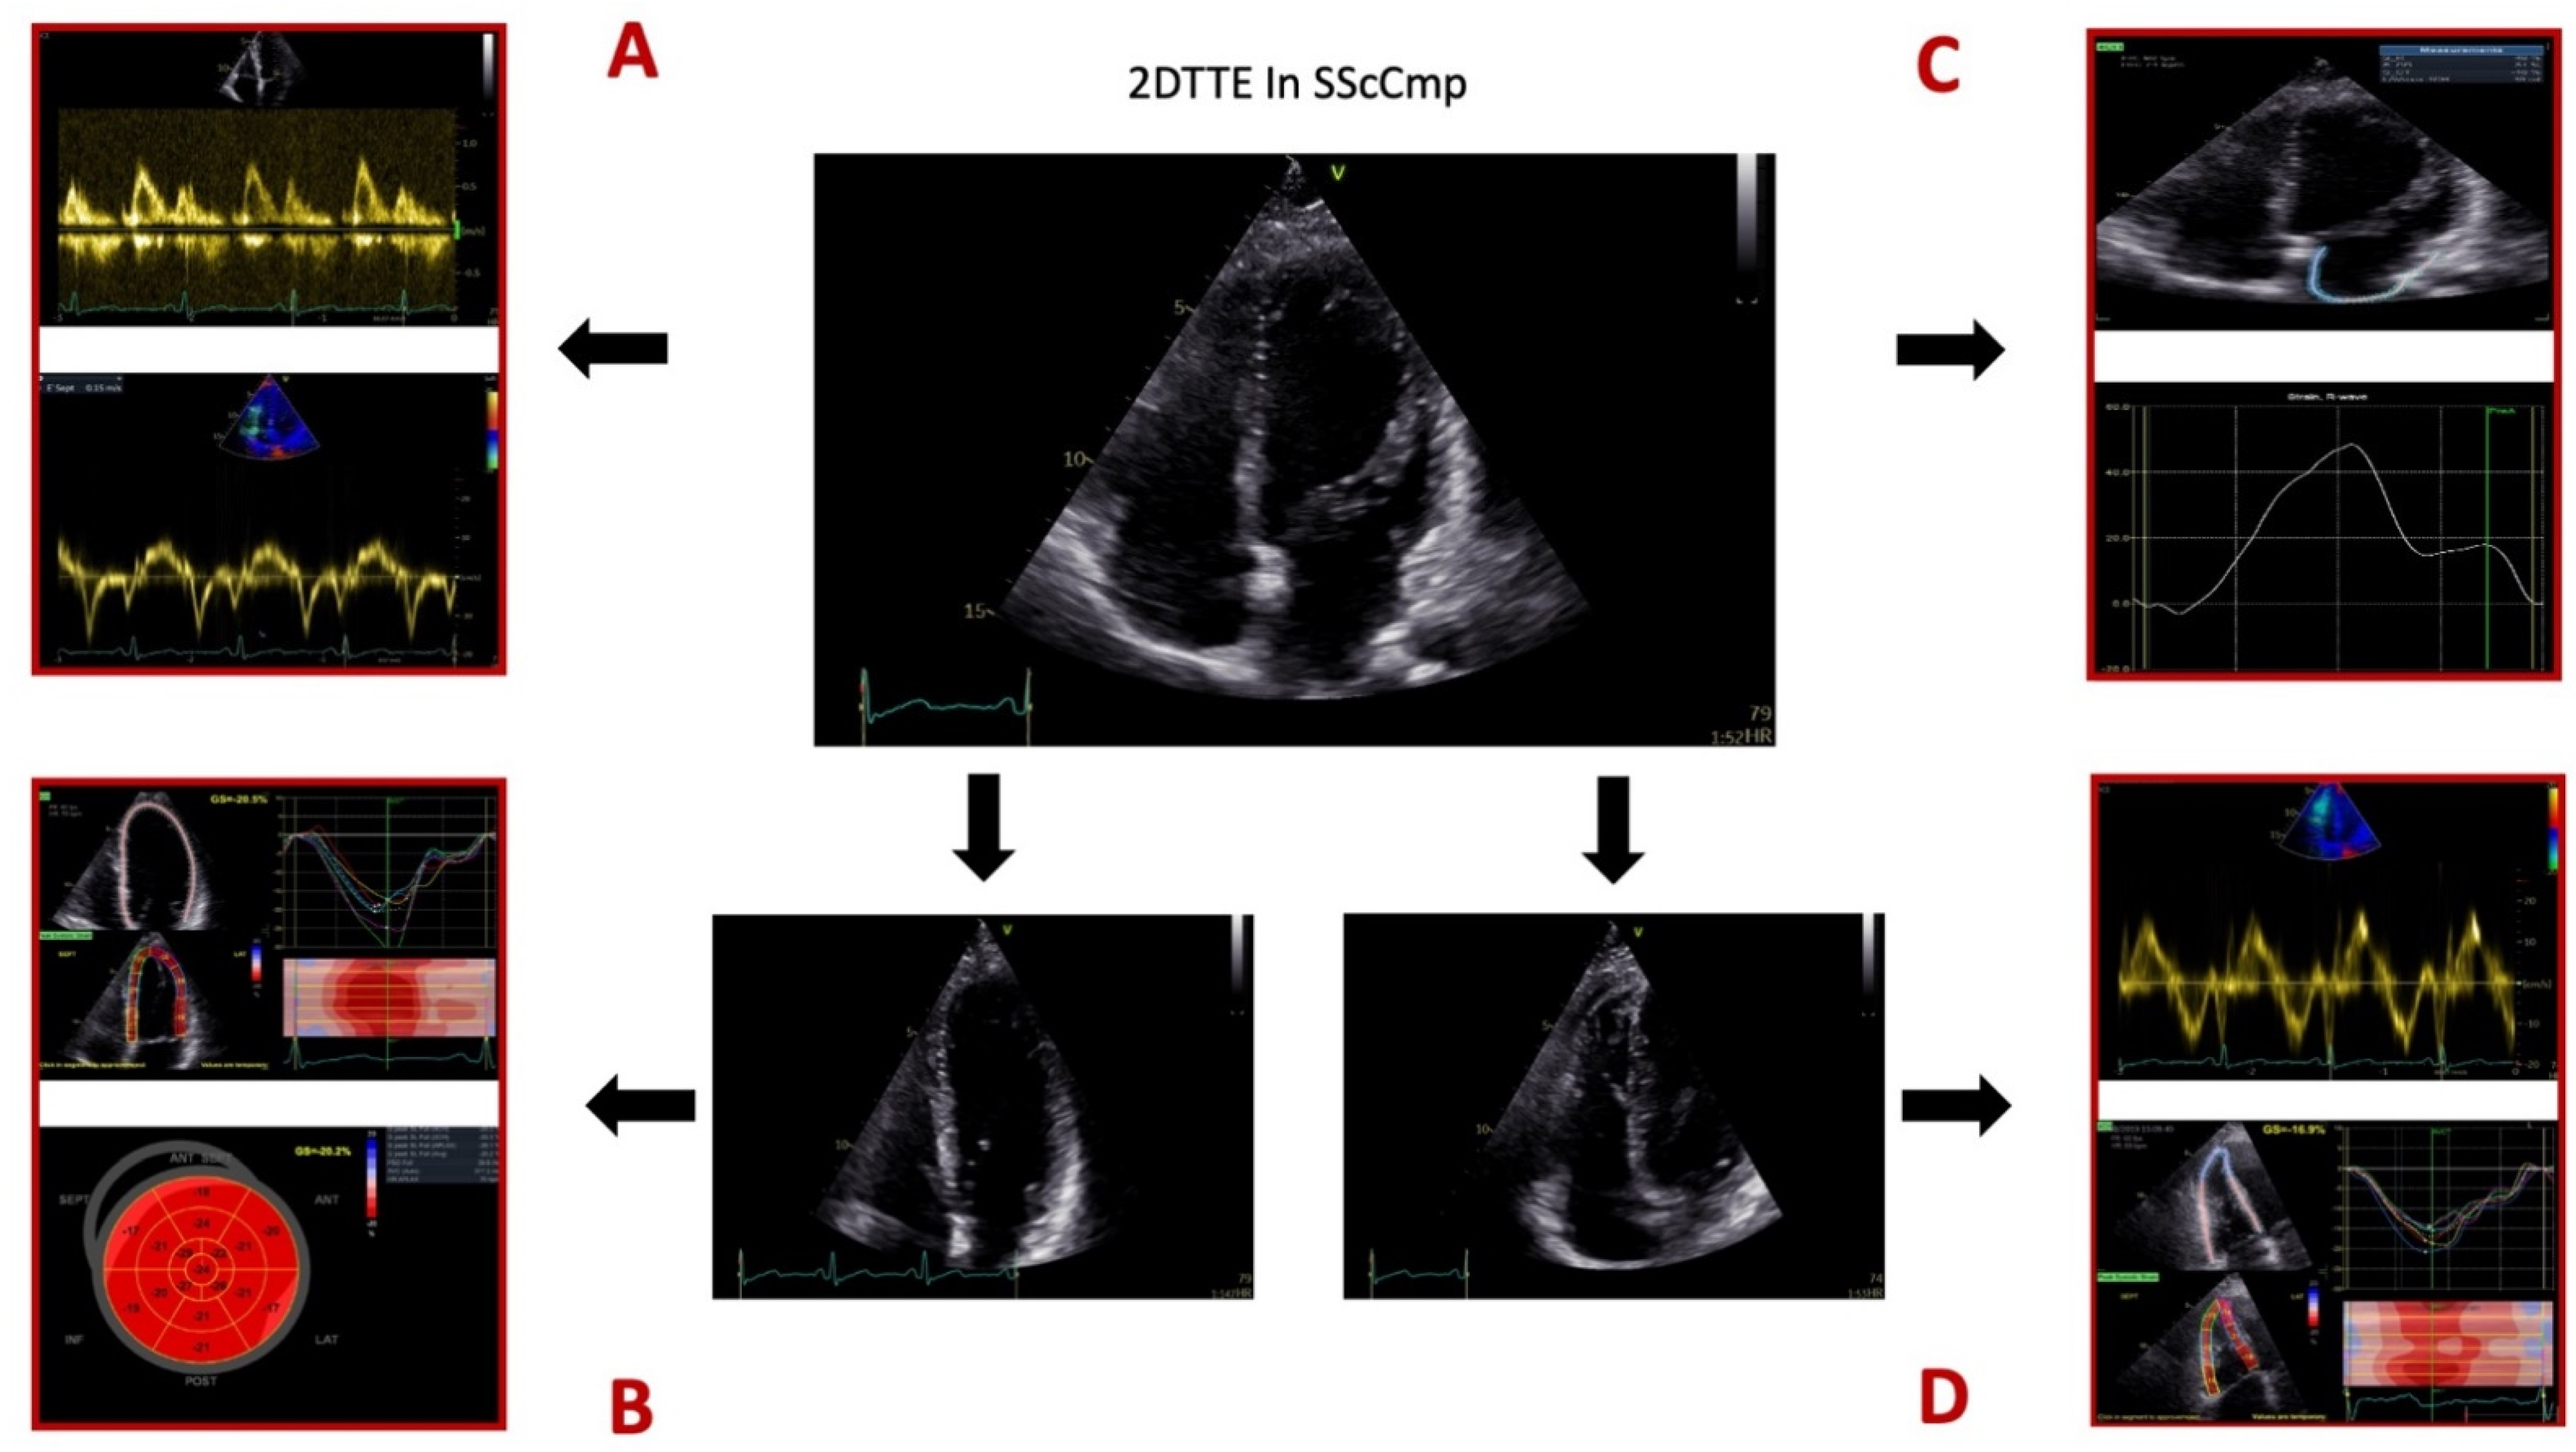

For a summary of different 2DTTE techniques employed for evaluating the SScCmp please see Figure 1.

Figure 1.

Different 2D transthoracic echocardiographic techniques used for evaluating the patients with systemic sclerosis and primary myocardial disease. Legend: Panel (A), mitral valve inflow profile by pulsed-wave (PW) Doppler, Tissue Doppler Imaging (TDI) for myocardial velocities. Panel (B), speckle-tracking echocardiography (STE) for assessing global longitudinal strain of the left ventricle (LV GLS). Panel (C), STE for assessing left atrial (LA) longitudinal strain. Panel (D), right ventricular (RV) evaluation comprised of TDI evaluation of RV free wall systolic velocity and RV free wall longitudinal strain. Images from the personal collection of the authors.